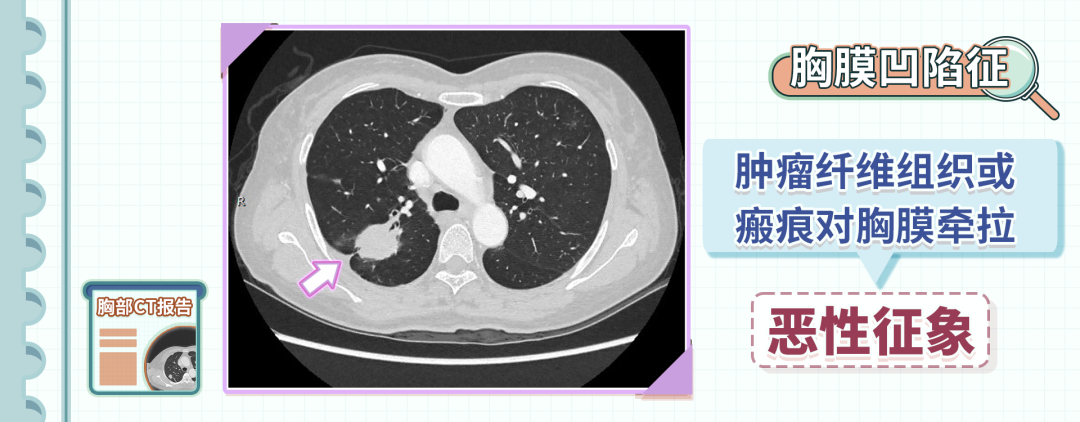

5、胸膜凹陷征

胸膜凹陷征是指结节和胸膜之间,可以看到三角形或者幕状的影像。

这个影像的尖端指向结节,基底在胸膜,是由于肿瘤里的纤维组织或者瘢痕对胸膜牵拉造成的,也是一个恶性征象,多见于肺癌。